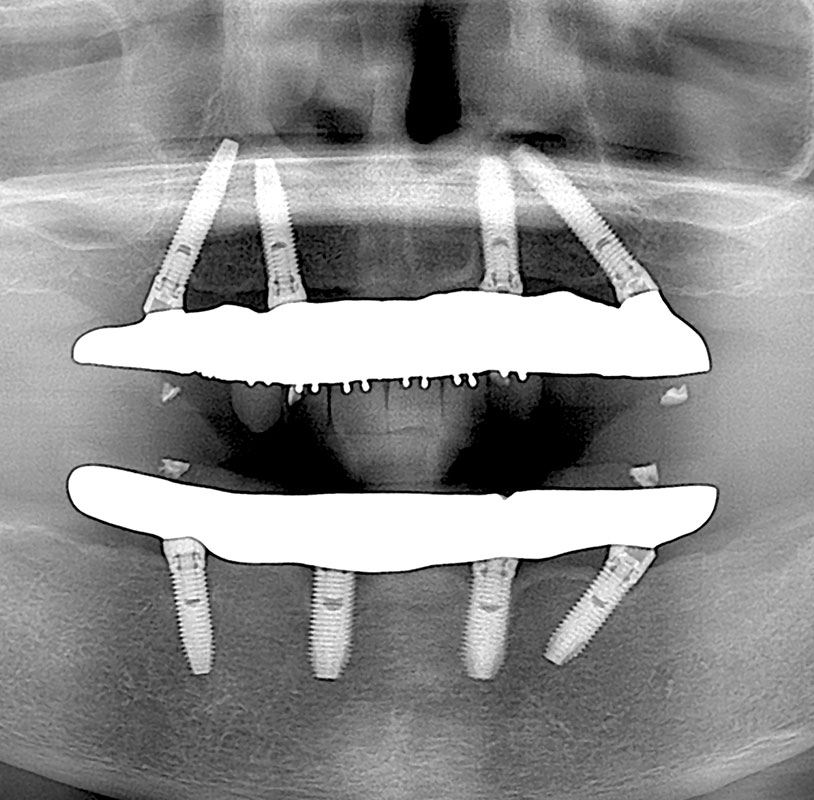

歯を失ってしまった場合、欠損部に人工歯根と人工歯を取り付け、機能性と審美性を回復させる治療です。豊富な治療経験と高い技術力をいかし、1本欠損から全部欠損まで、骨の少ない場合も含めて、要求の高い複雑なケースにも対応しています。痛みや腫れの少ない低侵襲インプラント治療のご提供を心がけています。

科学的根拠に基づいた的確な診査・診断と治療プラニング、高度な外科手技と合わせ、安全と信頼性に優れたインプラントシステムを導入し、高い成功率と満足を目指しています。

新型の高性能歯科用CT撮影機器とシュミレーションソフトとの併用により、術前の顎骨の状態や、神経・血管の走行が正確に確認でき、より安全にインプラント手術や外科手術を行えます。